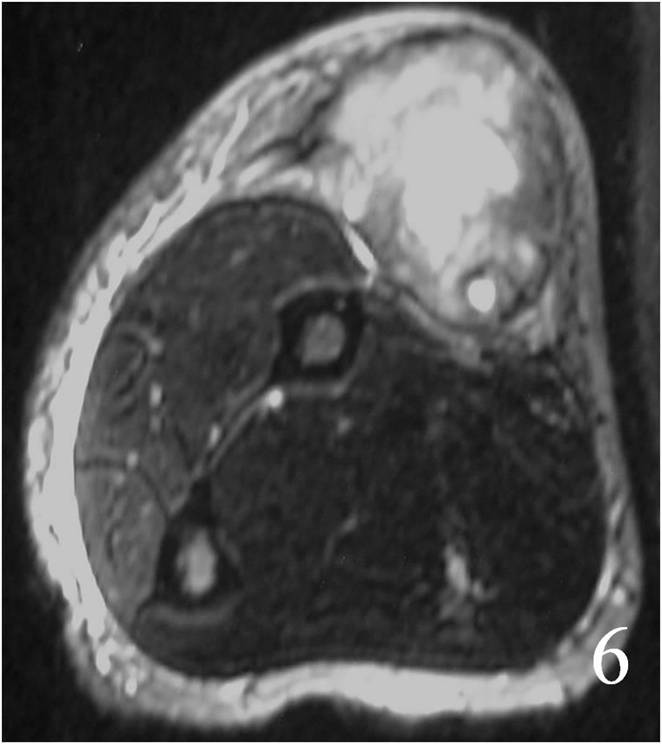

MRI

Large heterogeneous mass (Fig. 4, 5, 6)

Fig. 4 MRI of a leiomyosarcoma of the forearm shows a mass isointense to muscle on T1W image, heterogeneous on T2W (Fig. 5) and enhances with contrast T1W fat suppressed (Fig. 6)